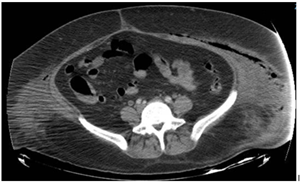

A 43-year-old female with morbid obesity (BMI 42), a history of type 2 diabetes diagnosed 12 years ago without treatment or follow-up, one cesarean section in 2011 and bilateral tubal occlusion in 2018. Who begins with sudden pain in the left inguinal region associated with swelling. She received analgesic treatment without improvement and decided to attend the hospital where is diagnosed with septic shock secondary to soft tissue infection. The results of the blood cytometry were leukocytes 21 000/mm, neutrophils 89%, lymphocytes 6%, hemoglobin 9 mg/dL, hematocrit 28%, and platelets 21 000/mm. Surgical drainage was done and a vulvar abscess was found, dissecting from the mount pubis to the ischiopubic fossa with necrotic tissue and fetid purulent material. During her postoperative period, she continued with purulent secretion outflow; a tomographic study showed the presence of fluid between the subcutaneous cell tissue and the muscular abdominal wall associated with subcutaneous emphysema (Figure 1 & 2). A reintervention was decided for surgical debridement and lavage, among the findings were: labile tissue with fetid necrotic edges, purulent secretion from the left genital area, inguinal region, abdominal subcutaneous cell tissue to the external oblique aponeurosis (Figure 3). In the postoperative period, multiple surgical lavages and debridements were carried out, followed by a VAC system. Nutritional parameters were below the acceptable level, parenteral nutrition was started and enteral nutrition with arginine boluses. A curve of nutritional parameters (albumin, prealbumin, ferritin and transferrin) was made prior to the establishment of the VAC system (Figure 4 & Table 1).

Figure 2 CT scan that reveals the extension through the abdominal wall.